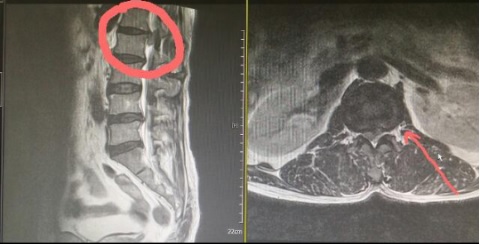

증상은 허리통증, 구부린 자세, 왼쪽 허벅지 당김 엉덩이통증, 발바닥 저림 , 극심통, 다리에 힘이 빠짐. 요추 1-2번 디스크 파열이었고 다리에 힘 빠짐이 심해 응급 수술로 진행되었습니다.